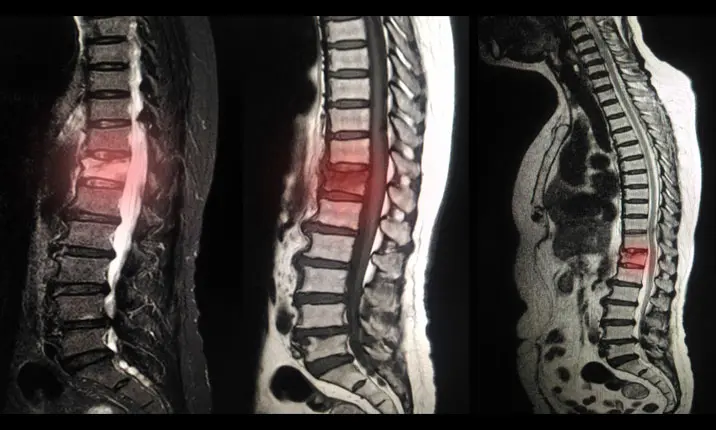

Chụp X-quang, chụp CT (chụp cắt lớp vi tính) hoặc MRI (chụp cộng hưởng từ) cột sống là những loại hình ảnh giúp chẩn đoán tình trạng thoái hóa cột sống. Nếu bạn đến gặp bác sĩ chuyên khoa vì cảm thấy cột sống không ổn, bác sĩ sẽ bắt đầu bằng việc hỏi về lịch sử điều trị và tiến hành khám sức khỏe toàn diện cho bạn.